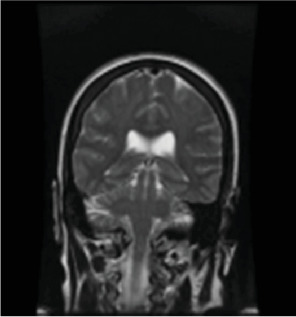

迟发性缺氧后白质脑病(DPHL)是一种罕见的诊断,可能与其他更常见的神经系统疾病(如紧张症)相似。虽然一氧化碳中毒很常见,但也可能是由于其他原因引起的缺氧,如药物过量或心脏骤停。由于其症状的迟发性和与其他疾病的重叠,最初可能被误诊。我们报告一名50岁女性患者,有抑郁史,在家中发现无反应、缺氧和发热,时间不详。最初担心的是败血症。最初的头部计算机断层扫描(CT)和脑部磁共振成像(MRI)正常。患者有横纹肌溶解伴继发性肾衰竭、肝休克和急性胰腺炎。药物稳定后,她的认知能力恢复到正常基线。然而,在住院10天后,她的精神状态恶化,表现为沉默、麻木、凝视、口服摄入量减少和毅力。怀疑继发于重度抑郁发作的紧张症。劳拉西泮向上滴定无结果。劳拉西泮无反应提示再次进行脑部MRI检查,显示双脑额叶、颞叶、顶叶和枕叶弥漫性白质改变。诊断为DPHL。随后,她开始服用卡比多巴/左旋多巴25/100 mg,情况有所改善,并出院至康复机构。

Delayed posthypoxic leukoencephalopathy (DPHL) is a rare diagnosis that may present similarly to other more common neurological conditions, such as catatonia. While often seen with carbon-monoxide poisoning, it can also be due to anoxia due to other causes, such as drug overdose or cardiac arrest. Due to the delayed nature of its symptoms and overlap with other conditions, it can be initially misdiagnosed. We present a 50-year-old female patient with a history of depression who was found unresponsive, hypoxic, and febrile at her home for an unknown amount of time. The initial concern was for sepsis. Initial computed tomography (CT) of the head and magnetic resonance imaging (MRI) of the brain were normal. The patient had rhabdomyolysis with secondary renal failure, shock liver, and acute pancreatitis. Once medically stabilized, her cognition returned to a normal baseline. However, 10 days into her hospitalization, her mental state deteriorated, displaying symptoms of mutism, stupor, staring, decreased oral intake, and perseveration. Catatonia, secondary to a major depressive episode, was suspected. Lorazepam was titrated upward without result. Lack of response to lorazepam prompted a repeat brain MRI, revealing diffuse white matter changes in the frontal, temporal, parietal, and occipital lobes of both hemispheres. A diagnosis of DPHL was made. She was then started on carbidopa/levodopa 25/100 mg with improvement and was discharged to a rehabilitation facility.